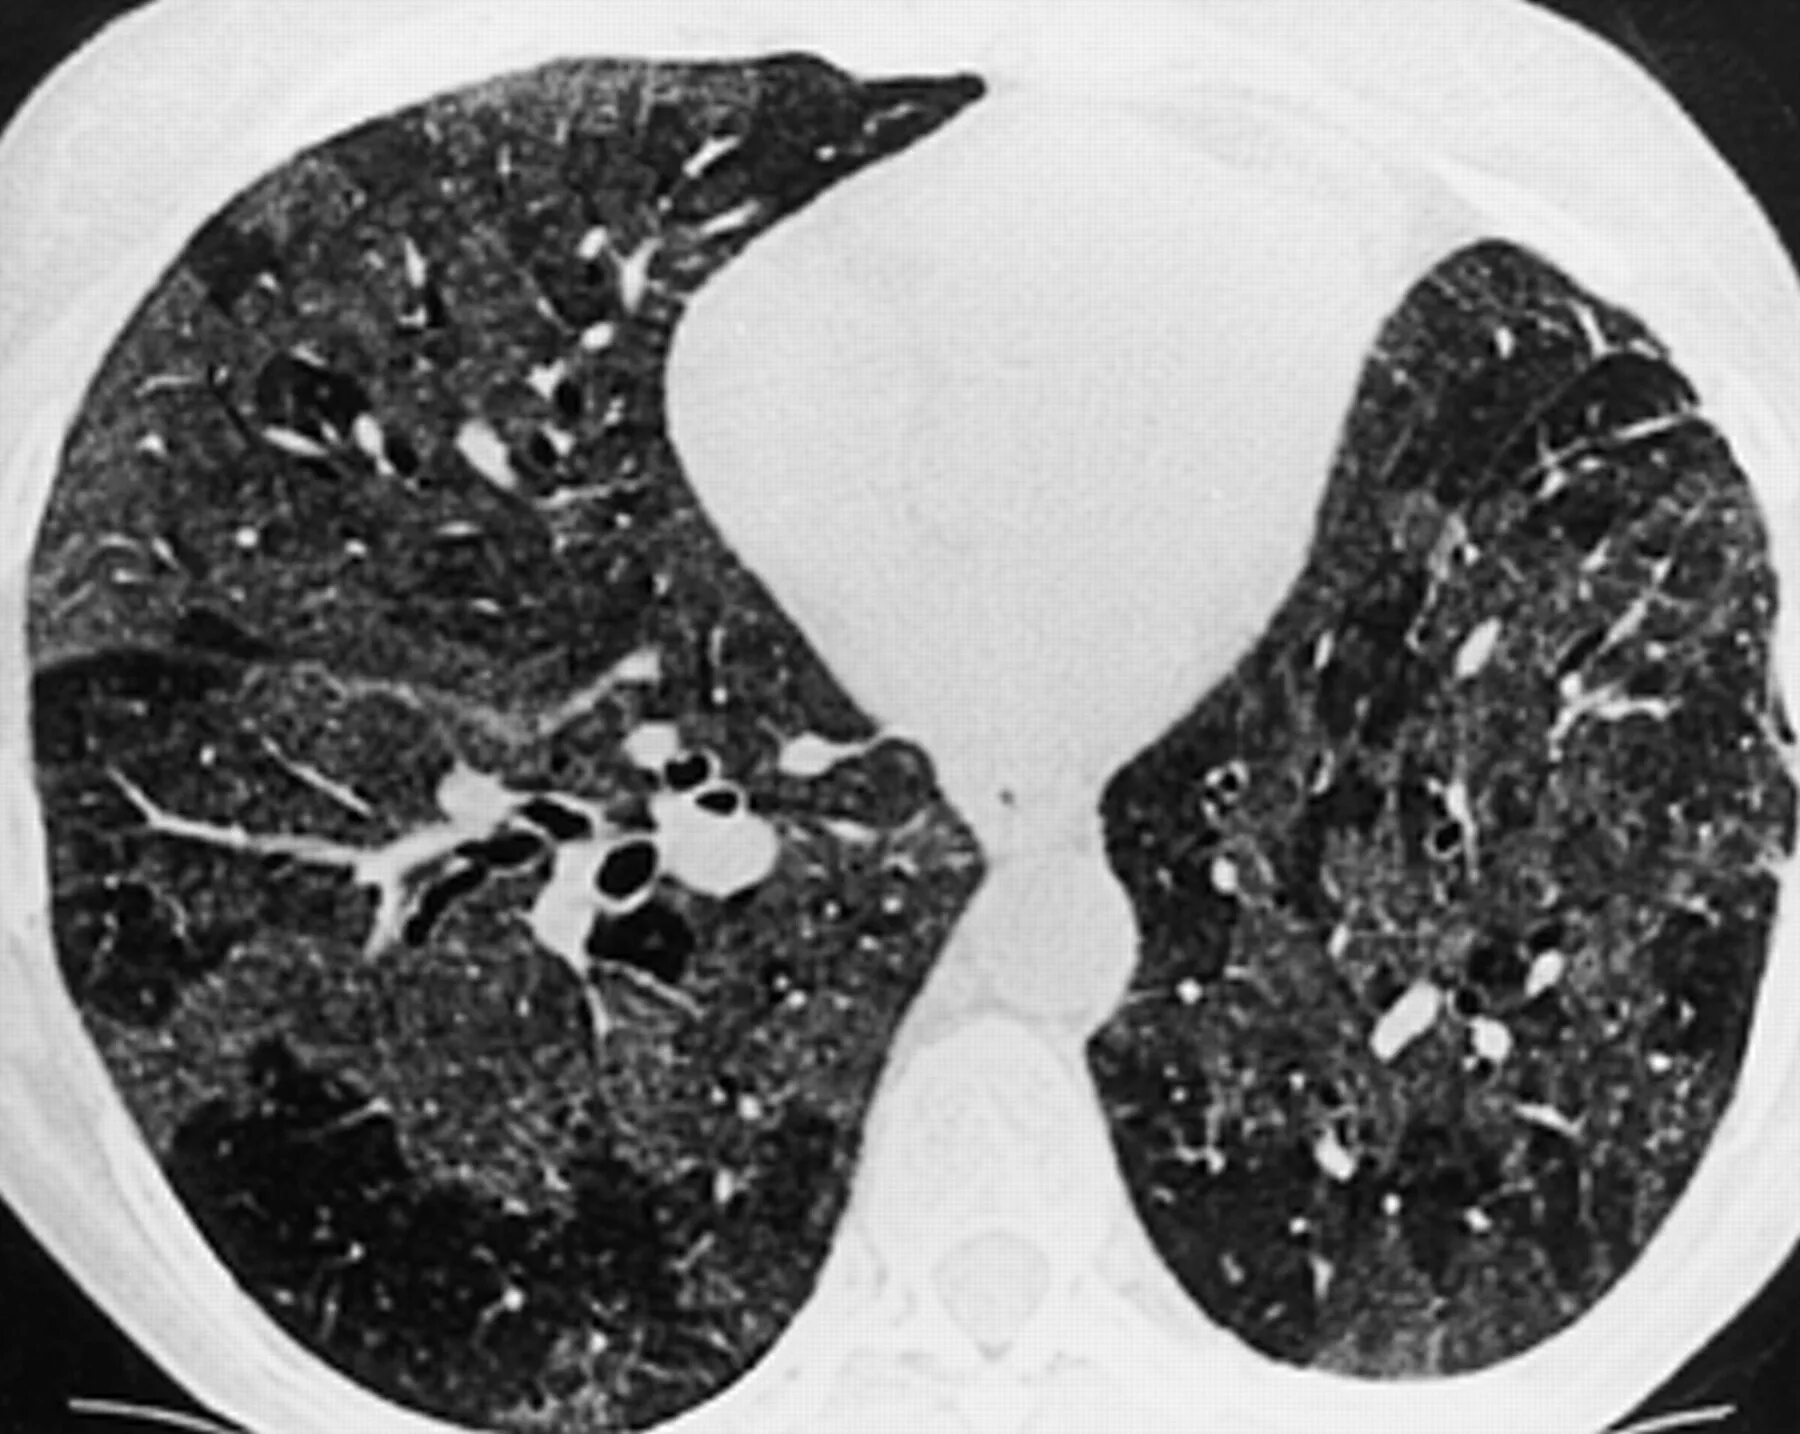

Заболевание кт